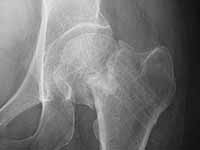

A male 31 years old treated elsewhere after not severe pelvic fracture 2 months ago, was managed non operatively. So the injury looked as a reason of his inability to elevate the leg. However at the recent x-rays the neck fractire was found. The patient already has been walking with partial weight-bearing.

Looking at the x-rays and the time since the injury, what is the optimal treatment for now? We discussed 1)leave as is, 2)2 cancellows screws as is, 3)valgus osteotomy. Total hip replacement looks unnecessary yet.

I would leave it as it is. Because surgical intervention will not be able to prevent osteonecrosis if it is going to be. MRI may be helpful to determine union if there is any and also gives an idea about the viability of the head.